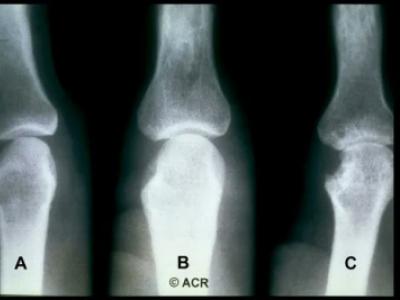

473 RA pts from the BeSt study were analyzed. for correlation betw joint cumulative inflammation and radiographic damage. Cumulative jt swelling was signif correlated w/ future xray damage/erosions, less so for tender only jts https://t.co/DQ06VYBDxm https://t.co/PfRWCcti8T